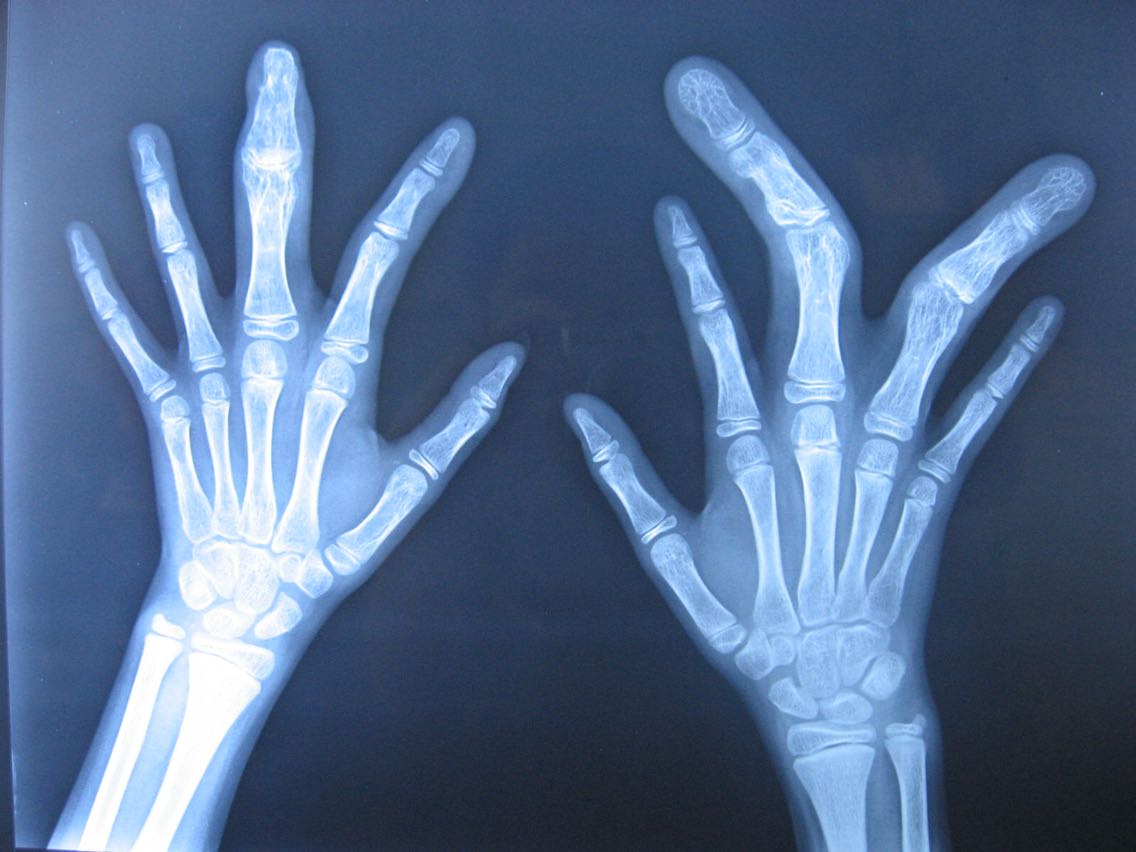

辅查:双手部X光片示:右手中环指、左手中指骨质较其余手指骨质粗大、变长,指间关节关节间隙变窄,并出现侧弯畸形改变。